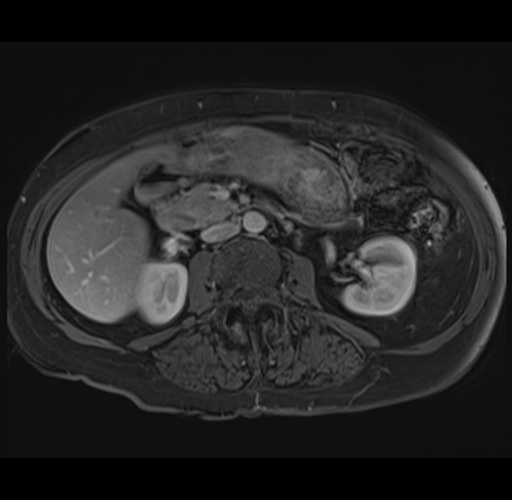

MRI T1